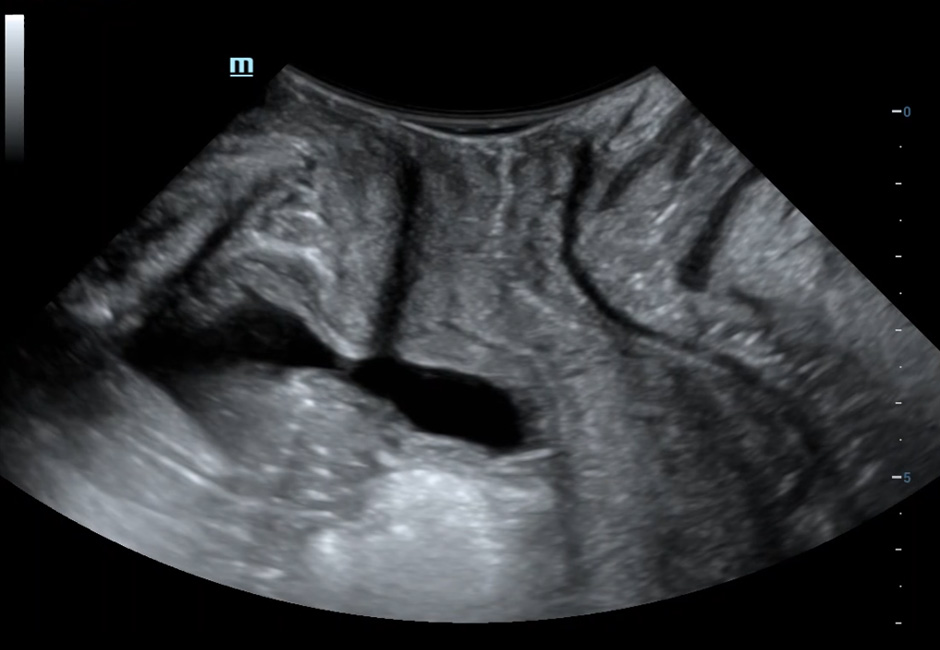

Transverse Section of The Anal Canal